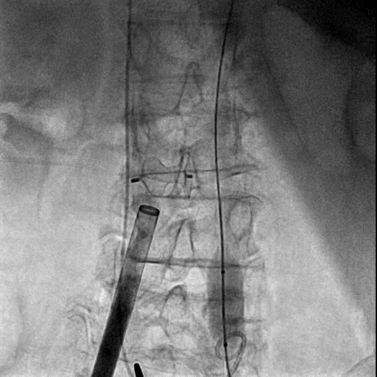

将0.014英寸导丝交换为超硬导丝后,置入22F大鞘达腹主动脉内。

经右侧股静脉沿超硬导丝置入22F大鞘达腹主动脉内